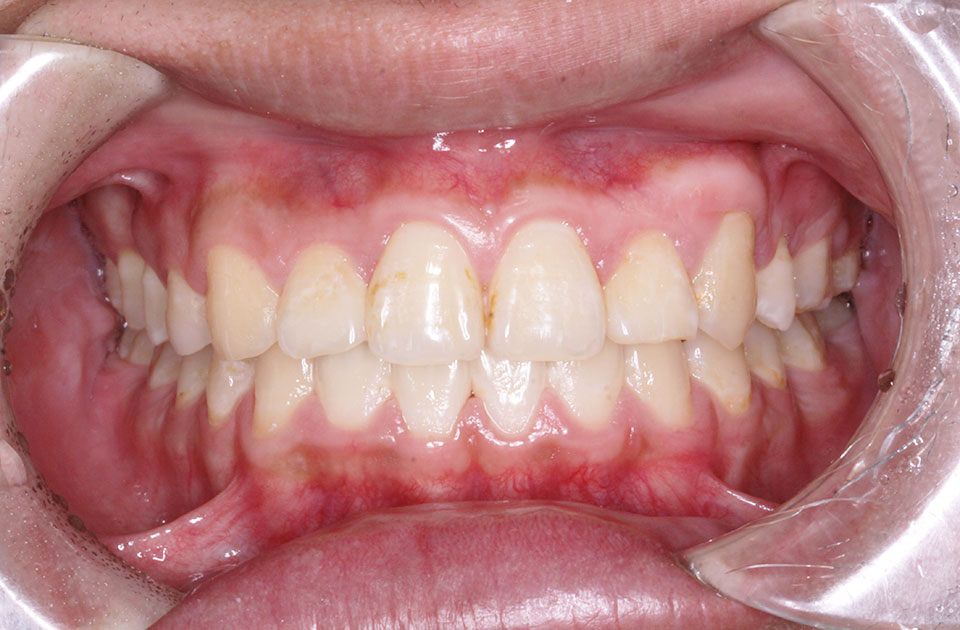

矯正後

矯正後 正面

矯正後 右側

矯正後 左側

治療法 上下顎マルチブラケット装置

治療期間 2年5ヶ月

治療費 抜歯¥5,500/本 基本矯正料¥770,000+処置料¥5,500(毎月)